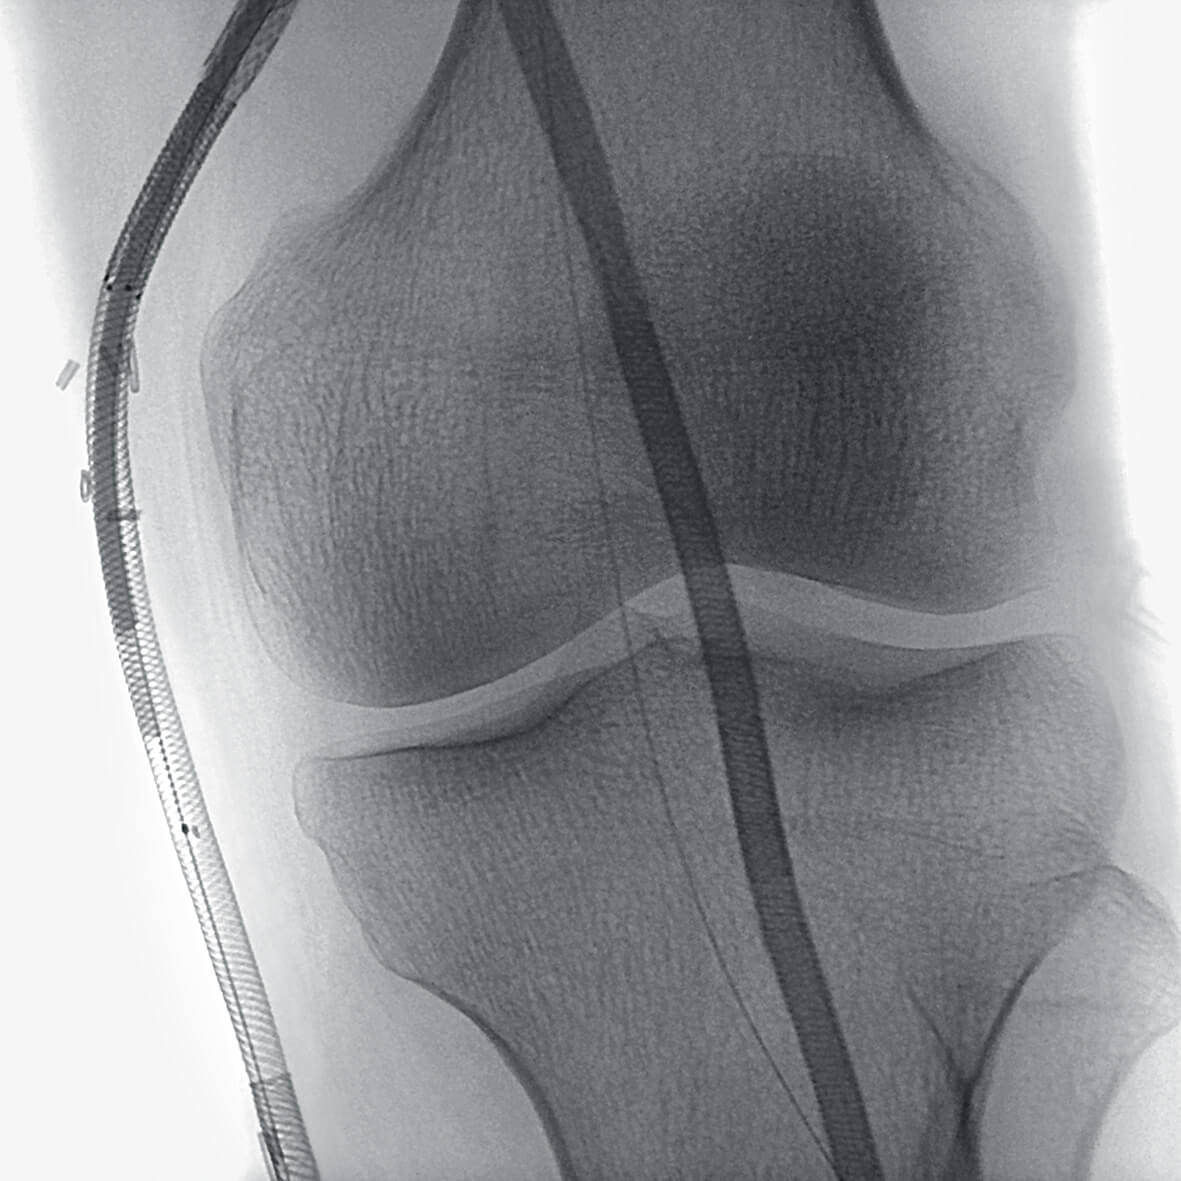

Изоцентрическое вращение штатива вокруг зоны обследования

В ходе проведения рентгенохирургических вмешательств, которые требуют полипроекционной визуализации, врач может зафиксировать центр области интересе и без изменения высоты операционного стола свободно перемещать штатив в трех плоскостях, при этом зона интереса всегда будет находиться в центре экрана.

Vision RFD 3D — первый передвижной рентгеновский аппарат, который обеспечивает изображения, ранее доступные только на стационарных системах. Плоскопанельный детектор формирует поле в 2,5 раза больше, чем усилитель рентгеновского изображения 9″. Увеличивается количество визуальной информации, постоянно доступной врачу на экране монитора с высоким разрешением.